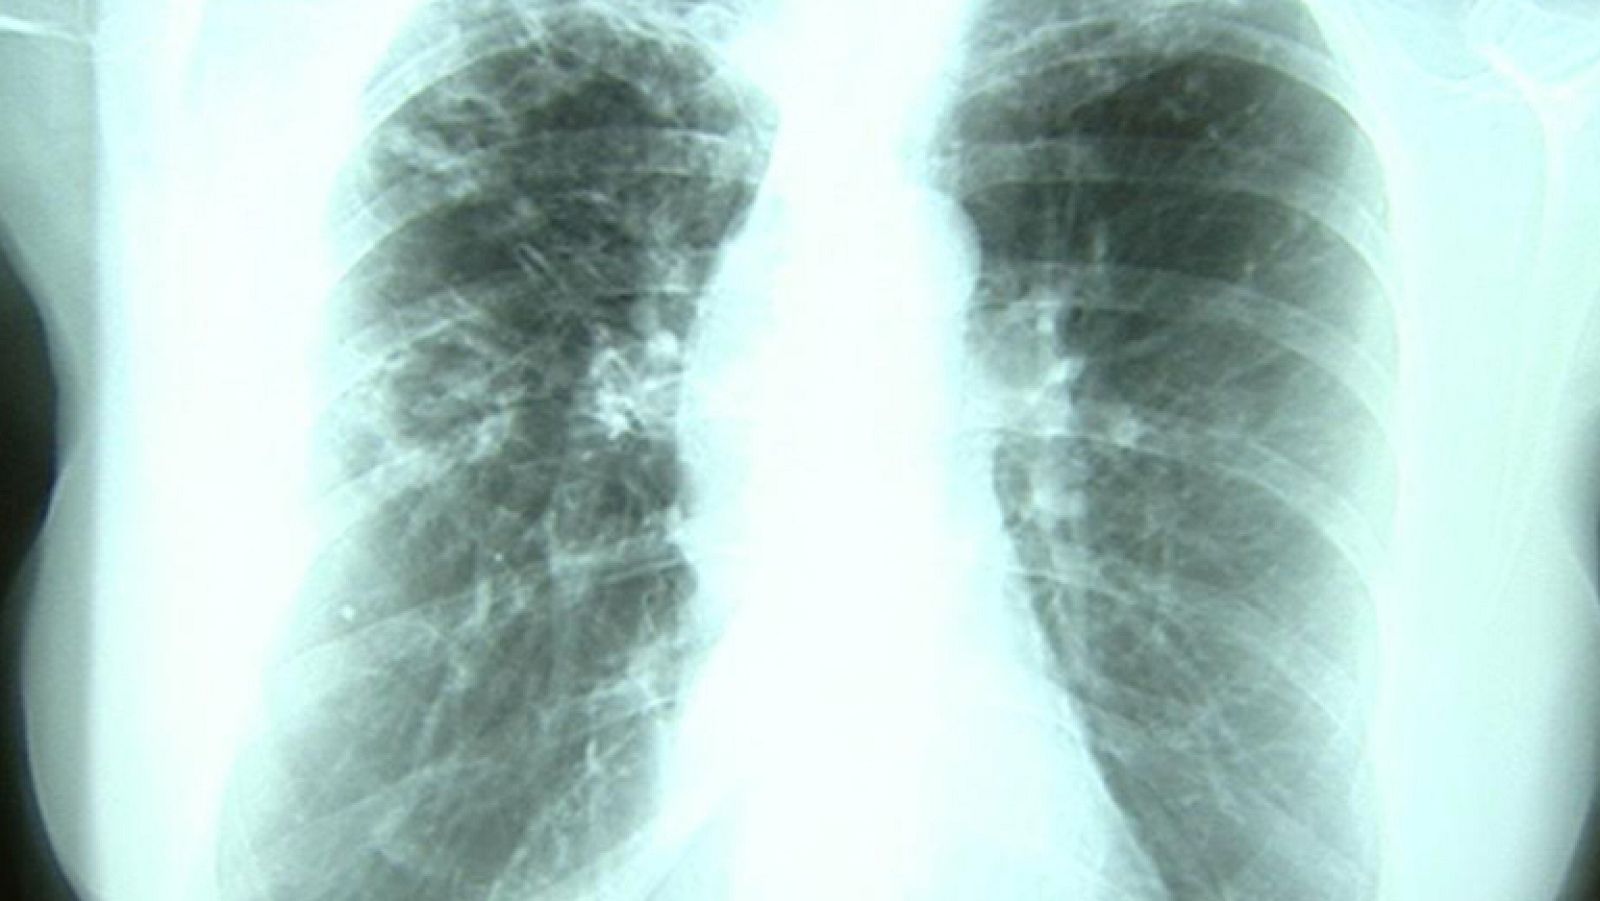

Día Mundial de la Tuberculosis, una enfermedad contagiosa por vía aérea

Hoy es el día Mundial de la Tuberculosis, una enfermedad contagiosa por vía aérea que afecta, sobre todo a los pulmones. En España, los emigrantes, seropositivos, diabéticos o fumadores son los grupos más sensibles. Un tercio de la población mundial está infectada.